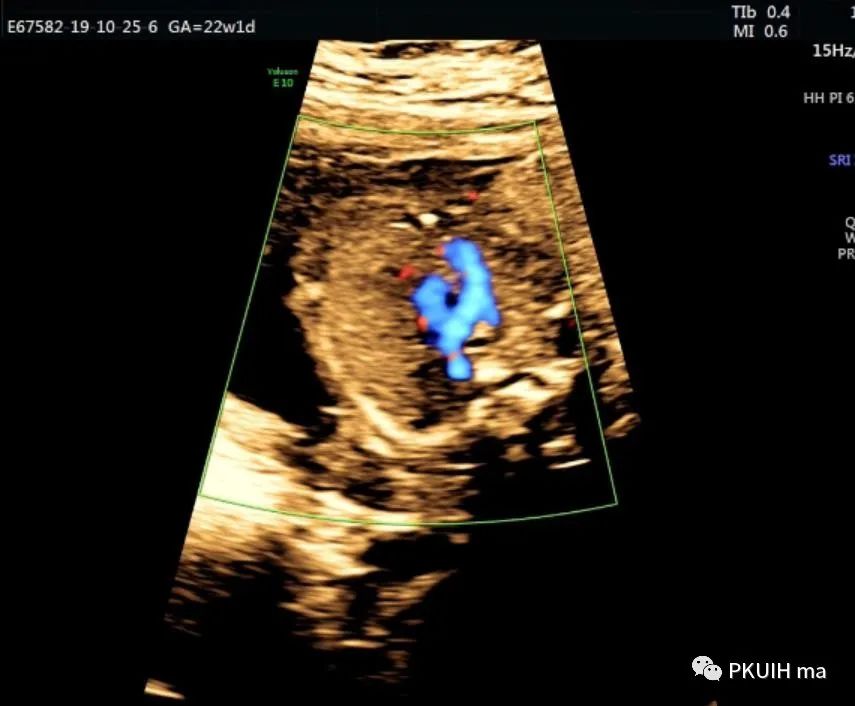

锁骨下动脉观察一般在主动脉弓水平横切面观察,显示左右锁骨下动脉像弓箭样向左右肩部走形。对于迷走的锁骨下动脉观察需要在三血管气管切面和主动脉冠状切面观察。右锁骨下动脉迷走在三血管气管切面可见一血管于主动脉弓降部发出自脊柱前方气管后方向右肩走行,在主动脉冠状切面显示主动脉弓降部见一血管迂曲向右肩部走行,频谱显示为动脉频谱。右锁骨下动脉迷走在三血管气管切面要和左无名静脉鉴别,左无名静脉汇入上腔静脉,频谱为静脉频谱,同时右锁骨下动脉也要和走形于气管后方汇入上腔静脉的奇静脉相鉴别,血流频谱有助于两者鉴别。

脊柱前方一红色血管为迷走的右锁骨下动脉,频谱为动脉频谱